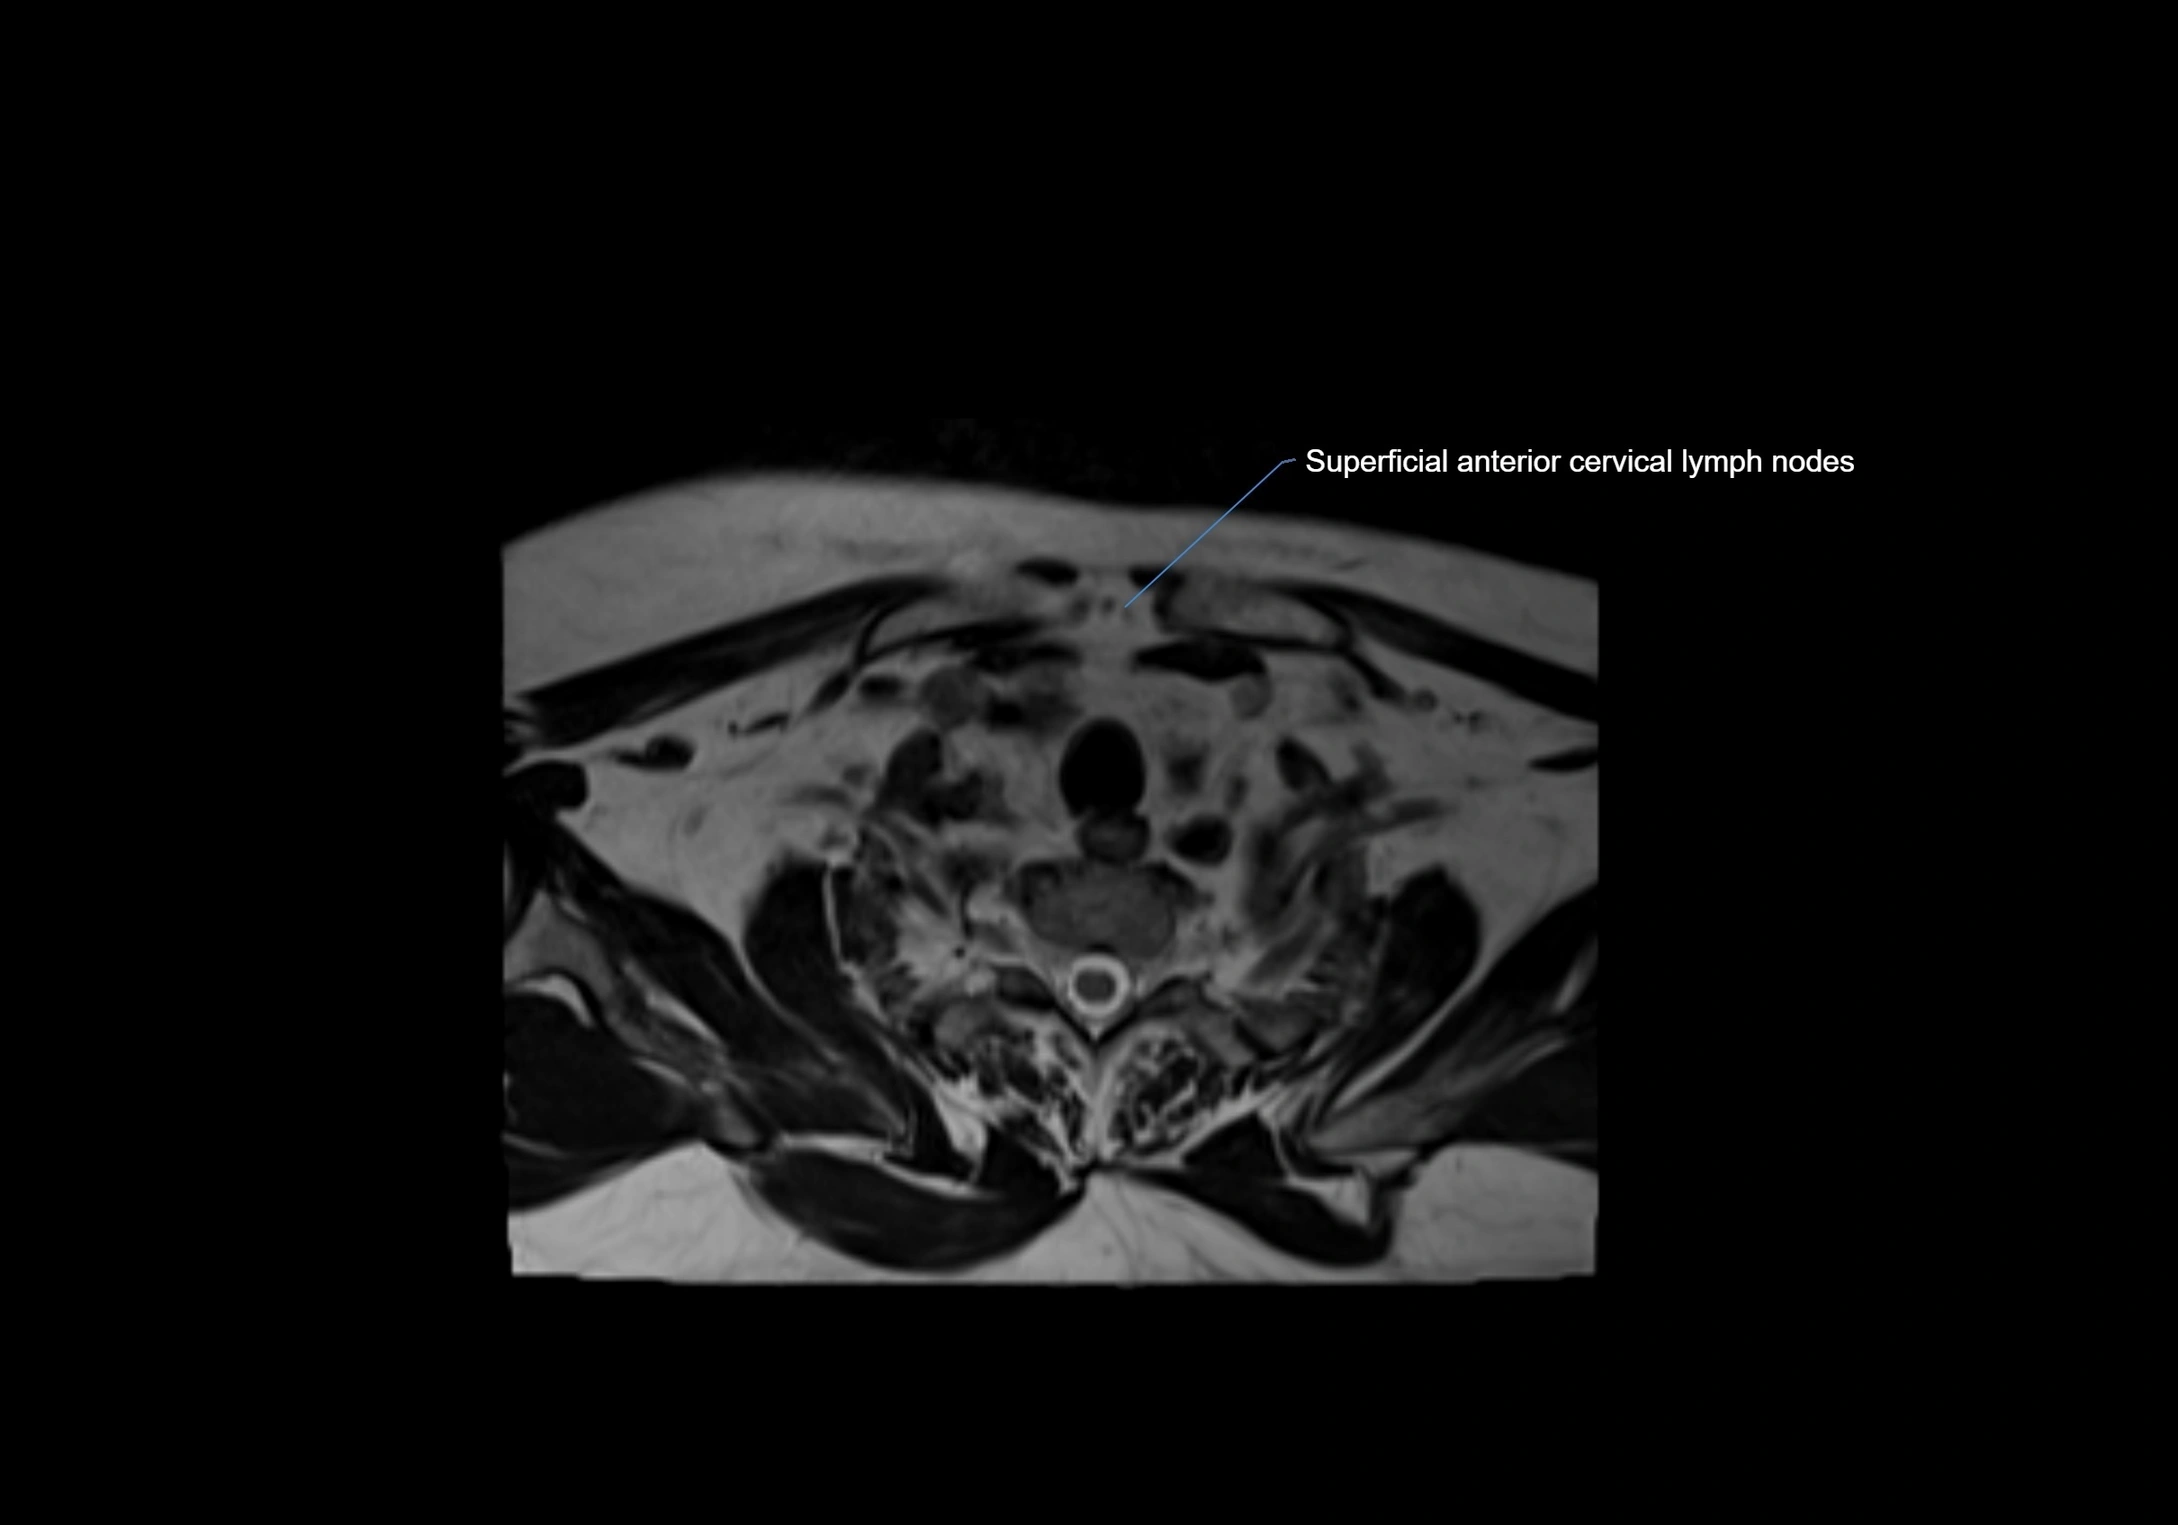

Location

• Found along primary lymph node chains, including preauricular, submandibular, parotid, and occipital regions

• Embedded in subcutaneous fat or superficial fascia, often lateral or posterior to primary nodes

MRI Appearance

T2-weighted images:

• Nodes show intermediate signal, with surrounding fat bright

• Useful for detecting edema, inflammation, or infiltration

CT Appearance:

• Nodes appear as small, soft tissue density structures embedded in subcutaneous fat near primary lymph nodes

• Surrounded by air in adjacent facial cavities or normal soft tissue, providing natural contrast

• Enlarged or pathological nodes appear as well-defined or irregular soft tissue masses